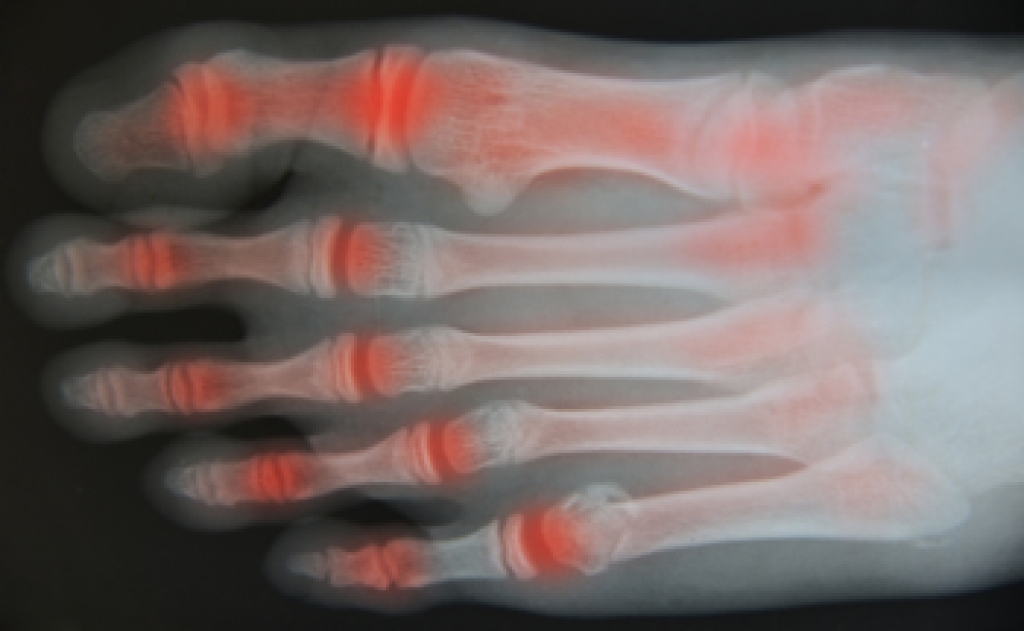

Swollen feet can also be caused by bone and tendon conditions, including fractures, arthritis, and tendinitis. Additionally, there may be skin and toenail conditions and an infection may cause the feet to swell. Patients who take medicine to treat high blood pressure may be prone to getting swollen feet.